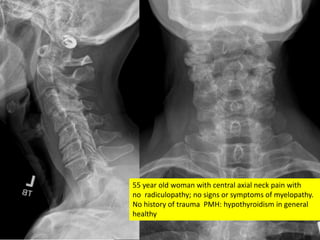

55 year old woman with central axial neck pain with

no radiculopathy; no signs or symptoms of myelopathy.

No history of trauma PMH: hypothyroidism in general

healthy

55 year oldwoman with central axial neck pain with no radiculopathy; no signs or symptoms of myelopathy. No history of trauma PMH: hypothyroidism in general healthy